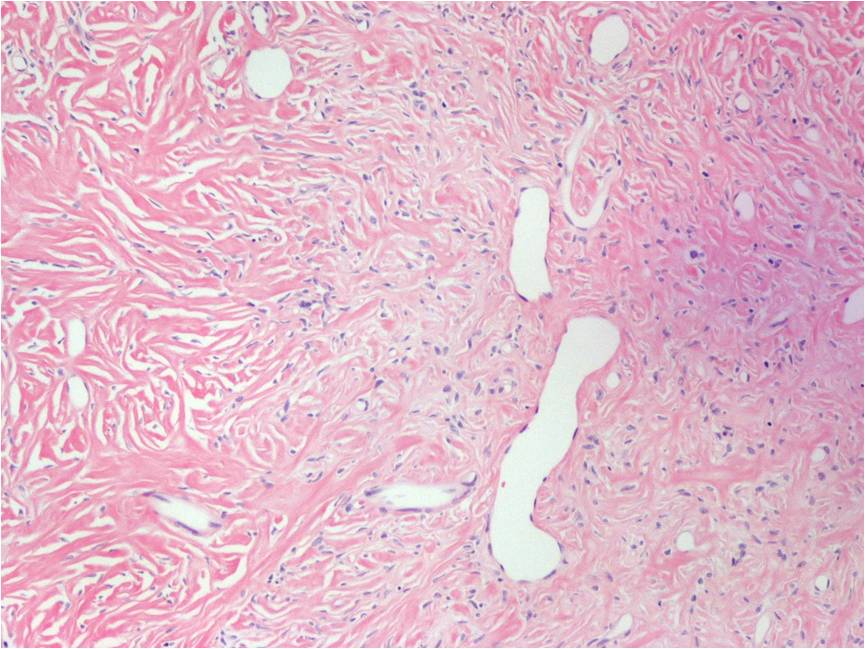

Low Grade Fibromyxoid Sarcoma is a low-grade malignancy by definition. Microscopically, tumors usually have myxoid and fibrous areas, admixed with hypo and hypercellular areas. Low grade fibromyxoid sarcoma is typically described as fascicular or whorled pattern of growth, with heavily collagenized stroma surrounded by epithelioid fibroblastic cells. Recurrences may show increased cellularity and mitotic activity (Fig. 6-8).

Fig. 6-8: Microscopic Pathology. Low (Fig. 5), intermediate (Fig. 6) and high (Fig. 7) power magnification H&E slides. Fusiform or spindled cells with moderate cellularity are easily distinguished. Diffuse whirled pattern is seen in all magnifications. Some areas demonstrate abrupt transition from collagenous areas to myxoid areas. (Fig. 5 & 6)